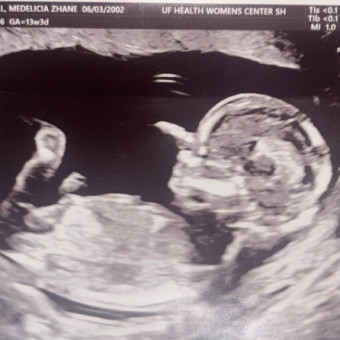

Mal’Jhené Kymani Jean

Medi Kitchell & Malachi Jean

Fort White, FL

February 14, 2026